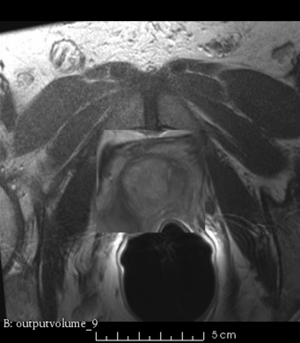

Case 9

Reference intraop volume

Reg Result Slicer 3.6 with ITKv3

Reg Result Slicer 4.4 with ITKv4